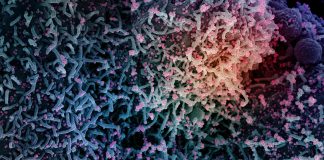

COVID-19 è una malattia infettiva respiratoria causata dal virus denominato SARS-CoV-2 appartenente alla famiglia dei coronavirus. Una malattia infettiva causata da un nuovo virus mai identificato prima negli esseri umani.